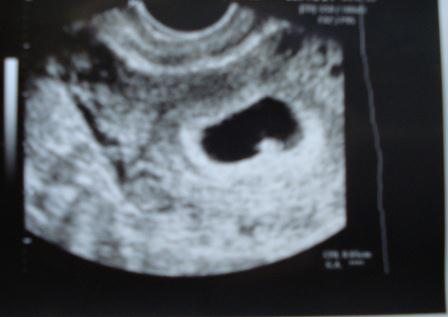

N és akkor jövök a nagy hírrel, képzeljétek babát várok!!! :P :P Spontán, simán, pikk-pakk össze jött.Alig hittem a szememnek amikor május 3-án cső pozitív volt a tesztem.Ma voltam UH-on és úgy néz ki minden oks, dobog a szívecske :lol:

Kép